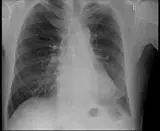

Over 2,100 interactive radiology cases, curated by radiologists for your level of training. Scroll, window, and view cases full screen โ€” just like on PACS. Click linked findings in each writeup to jump straight to them on the image. Cases include sample reports, a focused discussion section, original illustrations, and videos.

PACS์—์„œ ๊ธฐ๋Œ€ํ•  ์ˆ˜ ์žˆ๋Š” ๋ชจ๋“  ๋„๊ตฌ๋ฅผ ๊ฐ–์ถ˜ ์™„์ „ํ•œ ์ธํ„ฐ๋ž™ํ‹ฐ๋ธŒ ์ฆ๋ก€ — ์Šคํฌ๋กค, ์œˆ๋„์šฐ ์กฐ์ ˆ, ํ™•๋Œ€/์ถ•์†Œ, ํŒจ๋‹, ๊ณ„์ธก, ROI, ์ „์ฒด ํ™”๋ฉด ๋ชจ๋“œ๊นŒ์ง€ ์ง€์›ํ•ฉ๋‹ˆ๋‹ค.

์ฃผ์š” ์†Œ๊ฒฌ์„ ์ฆ๋ก€์— ์ง์ ‘ ํ‘œ์‹œํ•˜๋Š” ํ’๋ถ€ํ•œ ์ฃผ์„์ด ํฌํ•จ๋˜์–ด ์žˆ์Šต๋‹ˆ๋‹ค. ์ฆ๋ก€ ์„ค๋ช…์˜ ์—ฐ๊ฒฐ๋œ ์†Œ๊ฒฌ์„ ํด๋ฆญํ•˜๋ฉด ์Šค์บ” ๋‚ด ์ •ํ™•ํ•œ ์œ„์น˜๋กœ ๋ฐ”๋กœ ์ด๋™ํ•ฉ๋‹ˆ๋‹ค.

์–ด๋ ค์šด ์ฆ๋ก€๋ฅผ ์ •ํ™•ํžˆ ํŒ๋…ํ•˜๋Š” ๋น„๊ฒฐ์€ ๋Œ€๊ฐœ ์œ ์‚ฌํ•œ ์ฆ๋ก€๋ฅผ ์ด์ „์— ๋ณธ ์ ์ด ์žˆ๋Š”์ง€์— ๋‹ฌ๋ ค ์žˆ์Šต๋‹ˆ๋‹ค. ํฌ๊ด„์ ์ธ ์ง„๋‹จ ๋ชฉ๋ก์„ ์•„์šฐ๋ฅด๋Š” 1,900๊ฐœ ์ด์ƒ์˜ ์—„์„ ๋œ ์ฆ๋ก€๋กœ ์—ฐ์Šตํ•˜์„ธ์š”.